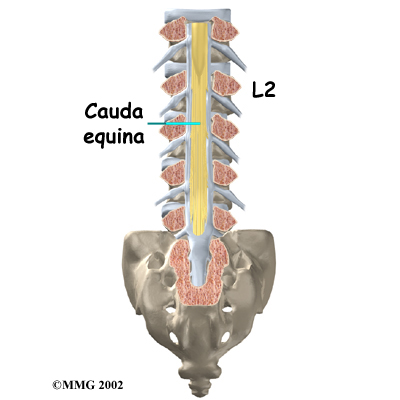

The back portion of the spinal column forms a . When the vertebrae are stacked on top of each other, these bony rings create a hollow tube. This bony tube, called the spinal canal, surrounds the as it passes through the spine. Just as the skull protects the brain, the bones of the spinal column protect the spinal cord.

The spinal cord only extends to the second lumbar (low back) vertebra. Below this level, the spinal canal encloses a bundle of nerves that go to the lower limbs and pelvic organs. The Latin term for this bundle of nerves is , meaning horse's tail.